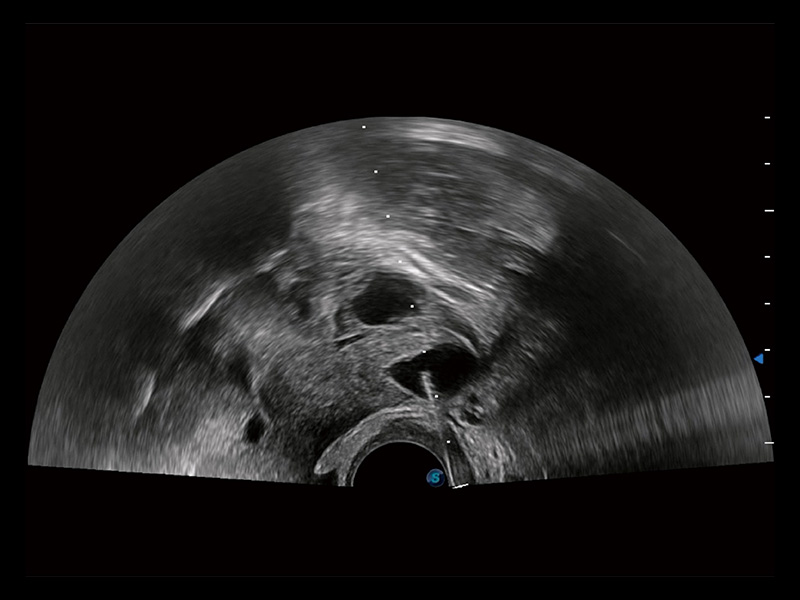

临床图

超声引导下胚胎移植